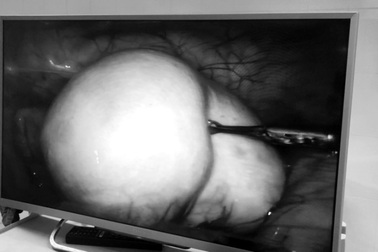

Đau bụng âm ỉ, nam thanh niên tá hỏa khi thấy mạc nối lớn xoắn như lò xo trong bụngThấy đau bụng âm ỉ, nam thanh niên 23 tuổi cứ nghĩ chỉ là đau ruột thừa nhưng không ngờ lại bị hoại tử mạc nối lớn. Hình ảnh nội soi cho thấy mạc nối lớn xoắn nhiều vòng như lò xo.